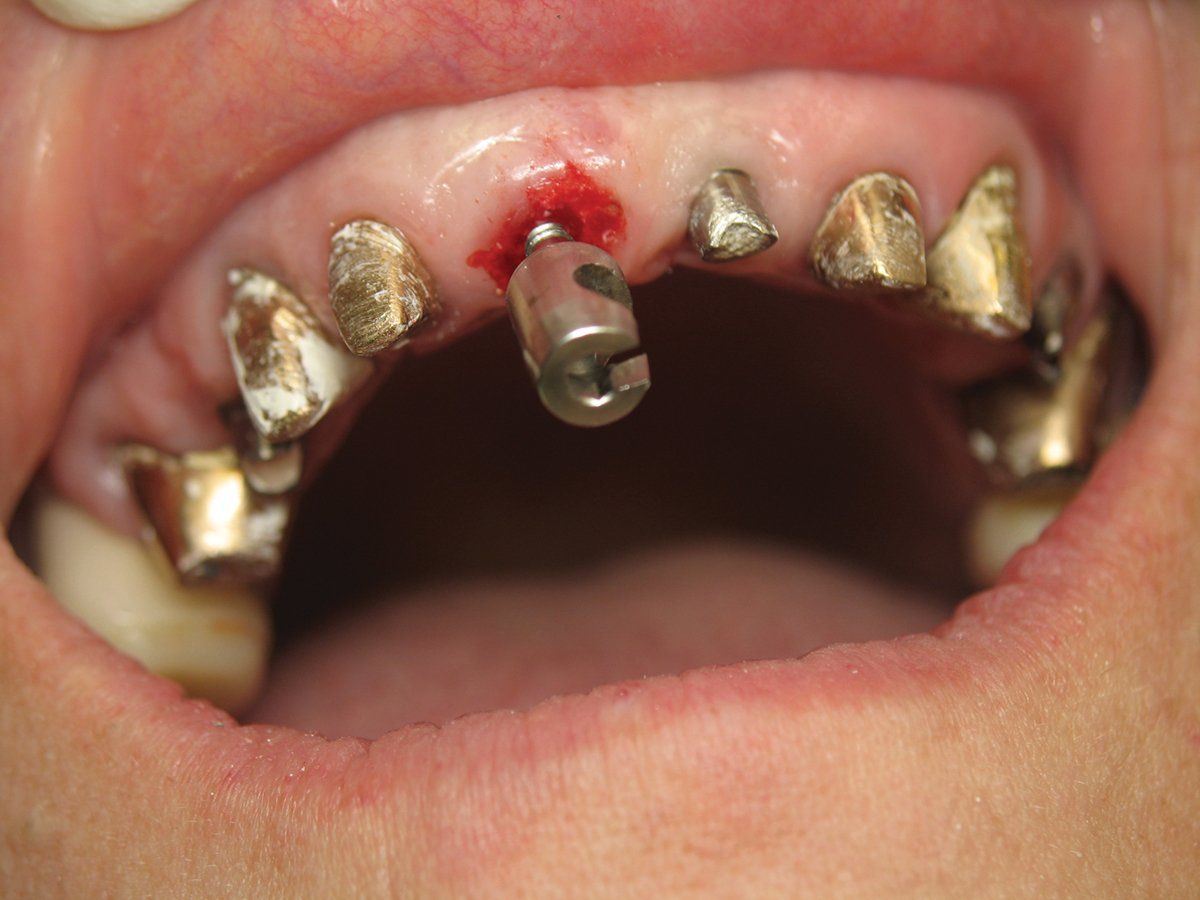

The specific technique involves using a special bur to drill into the pulp chamber and then threading a matching anchor into the tooth (Figure 3). A pulley system is utilized and a protective bite plate rests on the adjacent teeth and is attached to the anchor via a braided cable. By rotating a knob at the end of the instrument, pressure is applied in the vertical axis of the root. As you gently increase the pressure to the cable, it allows the periodontal ligament to stretch. The root is extracted from the socket when sufficient pressure is applied, making a popping noise (Figures 4). When this works, it feels like magic. Left behind is an intact socket with the soft tissue and bone preserved and ready for immediate placement of a dental implant (Figure 5).